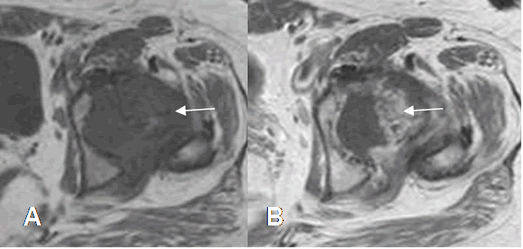

Fig 51. Sinovitis villonodular pigmentaria.

A: RM coronal en T2 y B: RM coronal en STIR. Derrame articular, con proliferación hipointensa de la sinovial, que rodean el cuello femoral. (Flechas).